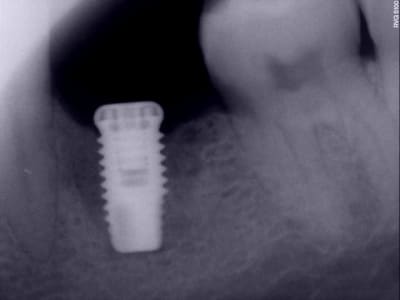

Ici, il est dommage que l'implant soit un peu court, ce qui peut entrainer sa perte par surcharge.

pas sûr que çà ne soit pas une perte de temps d'essayer de le conserver...perso je le dépose et j'en pose un tout beau, tout neuf 8 semaines plus tard mieux positionné...

implants courts...aujourd'hui on parle d'implants courts pour les moins de 8mm...un 4/10 c'est un implant standard...

les implants courts ne me font pas rêver non plus, mais ils peuvent parfois rendre bien service...